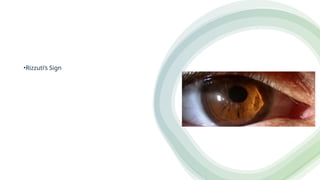

•Rizzuti’s Sign